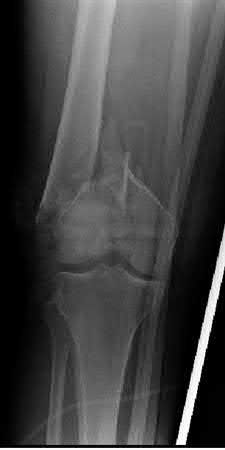

Buttress plating is most appropriate in which of the following clinical situations?

Figure A

Figure B

Figure C

Figure D

Figure E

Buttress plating is appropriate for a Shatzker Type I (see illustration C), as it can prevent collapse and axial deformity from shear or bending forces.

Figure B demonstrates an isolated medial femoral condyle fracture. Lateral locked plating is not an appropriate technique for this fracture.

The fracture shown in Figure B is an AO B type (partial articular fracture). This fracture is best treated with open reduction internal fixation through a medial approach, with lag screw and buttress plate fixation.

Figures A, C, D and E show supracondylar distal femur fractures that can be treated with ORIF with a fixed-angle device such as lateral locked plating.